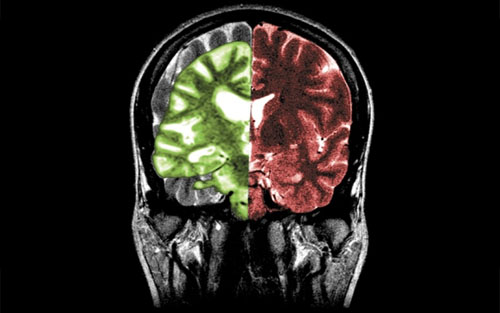

保留下来的三个针对β淀粉样蛋白的药物目前继续研究,研究观测对象不仅有阿尔兹海默病患者,而且包括无症状高危人群。研究发现,阿尔兹海默病高危人群可在症状出现、β淀粉样蛋白斑块形成、皮层萎缩前10年出现影像学异常。这些研究确定这些药物是否能预防或延缓疾病的发生。研究预计将在6年后完成。学术领域和医药企业现在已经有共同的认识,这已经是验证“β淀粉样蛋白瀑布”假说正确的最后机会。在担心的同时,人们开始将希望的目光转向ApoE。

阿尔兹海默病发生可能存在两个独立的通路,分别是b淀粉样蛋白依赖和非依赖通路。动物实验和人类患者,ApoE4可强烈促进b淀粉样蛋白在大脑组织中沉积,另外ApoE3和阿尔兹海默病没有关系,但是ApoE2则能避免阿尔兹海默病发生,减少b淀粉样蛋白在大脑组织中沉积。该疾病也存在不依赖于b淀粉样蛋白通路。当神经元受到应激刺激时,能通过合成ApoE修复细胞损伤,但坏的ApoE4能破坏线粒体,改变细胞骨架。Holtzman说,这两种阿尔兹海默病机制的相对重要性目前仍不清楚,但是他认为如果将坏的ApoE4转变成为没有毒性的类型,将对阿尔兹海默病具有治疗作用。